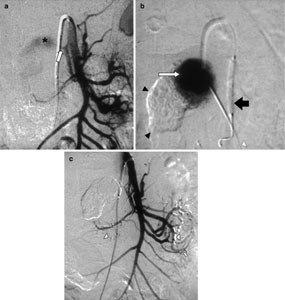

Percutaneous Glue Embolization of a Visceral Artery Pseudoaneurysm in a Case of Sickle Cell Anemia

Although aneurysmal complications of sickle cell anemia have been described in the intracranial circulation, visceral artery pseudoaneurysms in this disease entity have not previously been reported in the literature. Conventional treatment of visceral pseudoaneurysms has been surgical ligation or resection of the aneurysm. Transcatheter embolization has emerged as an attractive, minimally invasive alternative to surgery in the treatment of these lesions. In certain situations, however, due to the unfavorable angiographic anatomy precluding safe transcatheter embolization, direct percutaneous glue injection of the pseudoaneurysm sac may be considered to achieve successful occlusion of the sac. The procedure may be rendered safer by simultaneous balloon protection of the parent artery. We describe this novel treatment modality in a case of inferior pancreaticoduodenal artery pseudoaneurysm in a patient with sickle cell anemia. Although a complication in the form of glue reflux into the parent vessel occurred that necessitated surgery, this treatment modality may be used in very selected cases (where conventional endovascular embolization techniques are not applicable) after careful selection of the balloon diameter and appropriate concentration of the glue–lipiodol mixture.

Figure 1

Figure 2